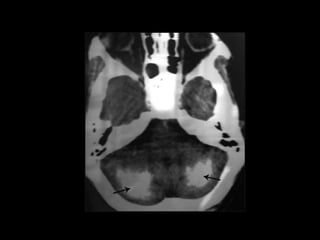

• Papilledema and calcification of the basal ganglia are other

signs of chronic hypocalcaemia.

Chronic hypoparathyroidism

• hypocalcemia ,Hyperphosphatemia with a low

parathyroid hormone(PTH) level is diagnostic.